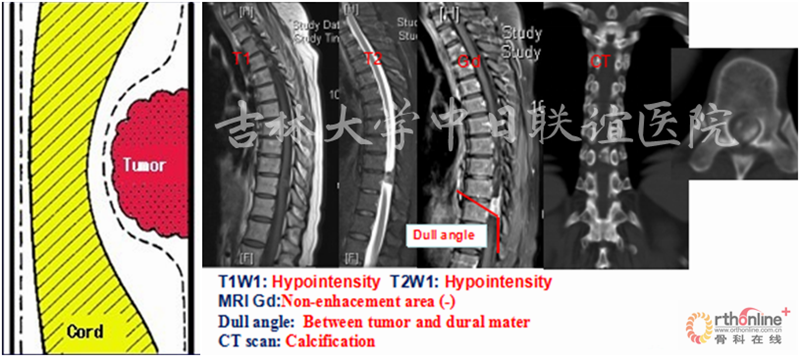

胸腰段X线/CT:未见明显异常

MRI:T1W1:相对脊髓呈等信号;T2W1:相对脊髓呈略高信号,瘤体与硬膜呈锐角,脑脊液在瘤体上缘增宽呈“杯口征”(瘤体位于硬膜下);MRI Gd:肿瘤边缘明显强化,瘤体中央伴有不均匀性增强。肿瘤与脊髓之间呈锐角,形成“肩胛征”,脊髓呈鸟嘴样改变(髓外)。

二、影像学表现:

X线平片和CT检查均需要依据钙化或肿瘤引起的明显骨质改变而检出病灶,阳性率较低,但是有助于了解脊柱的稳定程度、对手术方案的制定提供帮助;脊髓造影为有创性检查,通过肿瘤与造影剂的作用(如表现为充盈缺损等)对肿瘤的定位诊断有一定的帮助,但是对于肿瘤定性存在困难。MRI对椎管内软组织分辨率高并且能够避免骨骼的伪影,根据不同肿瘤相对特征性的MRI表现可以获得较为准确可靠的定位及定性诊断,有利于术前制定合理的手术方案。

神经鞘瘤(Neurinoma)

脊膜瘤(Meningioma)